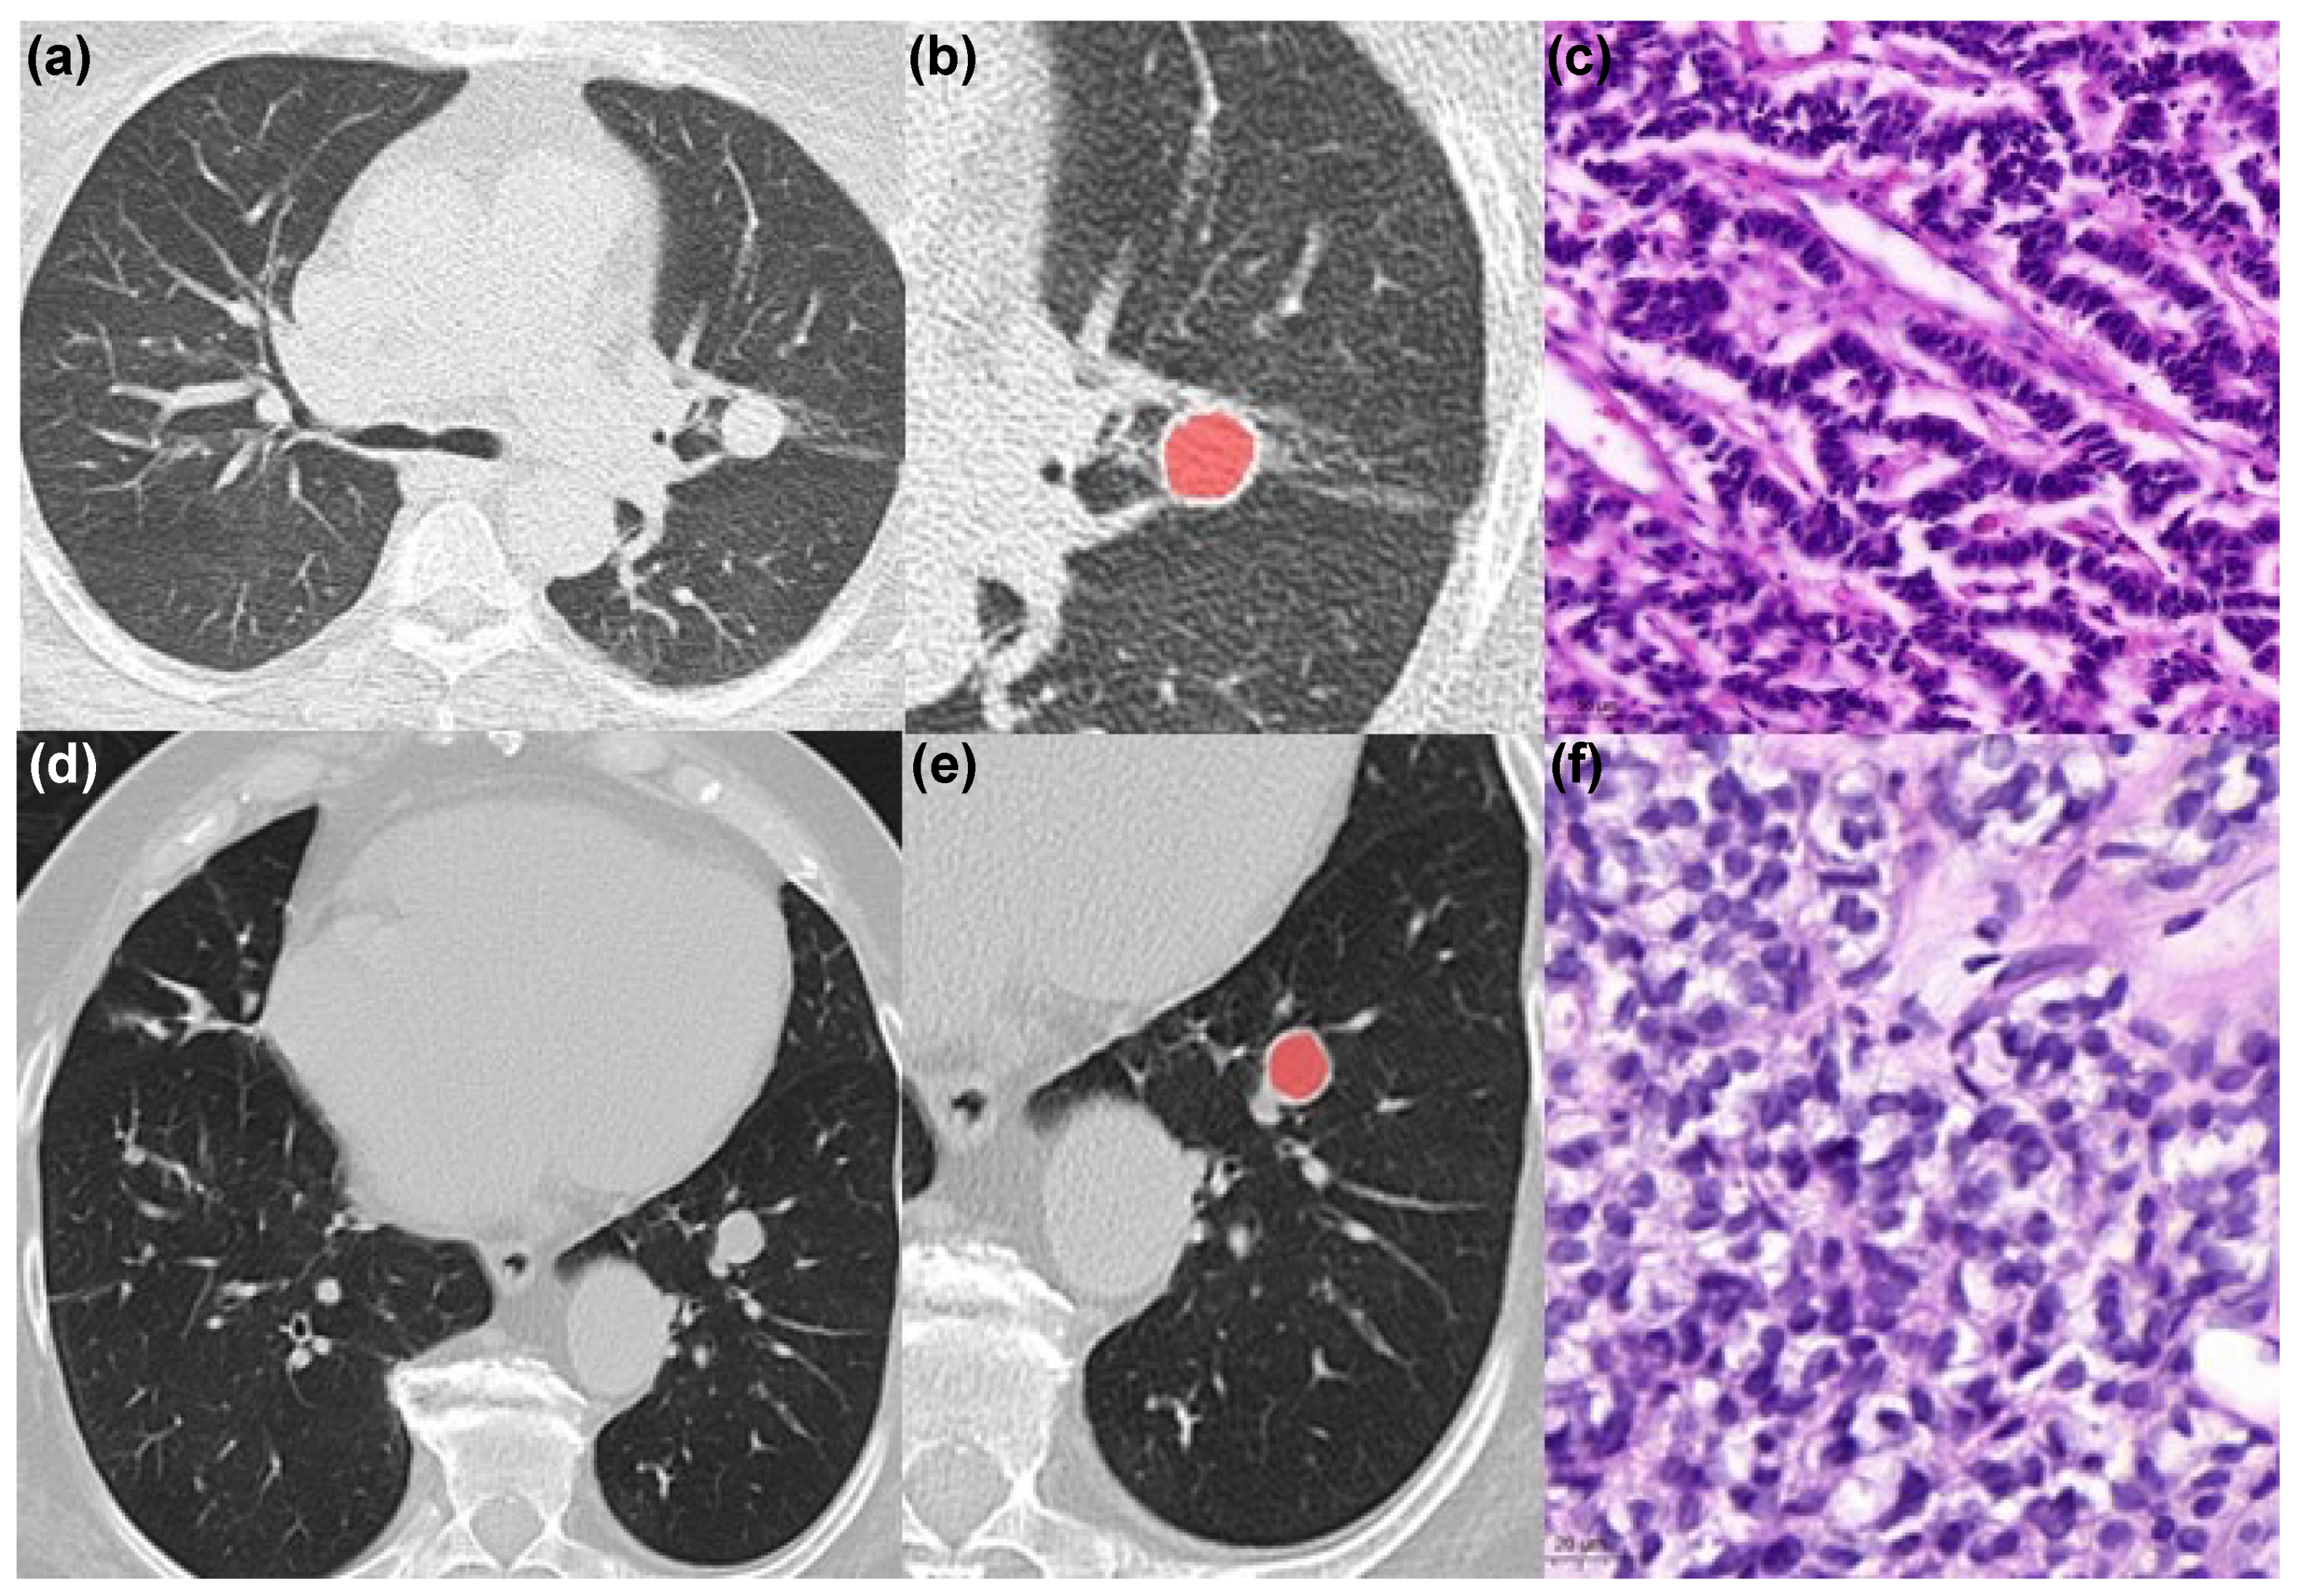

CT Texture Analysis of Pulmonary Neuroendocrine Tumors—Associations with Tumor Grading and Proliferation

2.2. Image Analysis

2.3. Texture Analysis

2.4. Histopathology Analysis